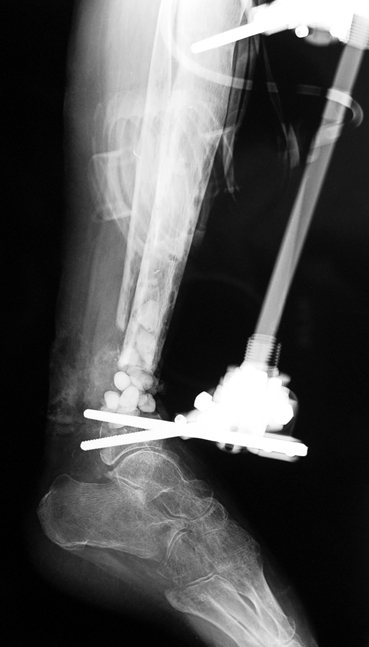

Vaka 2